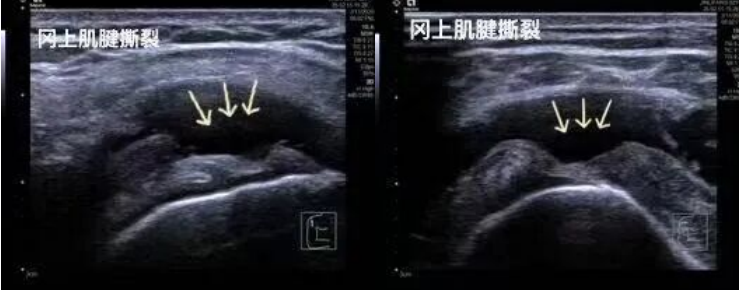

1.运动损伤:肩袖撕裂、网球肘、跟腱断裂、肌肉拉伤等。

2.高分辨率与实时动态成像:超声波可捕捉毫米级的软组织细节(如肌腱纤维的撕裂、滑膜增生),并能实时显示关节屈伸、肌肉收缩等动态过程,辅助医生精准评估功能异常。